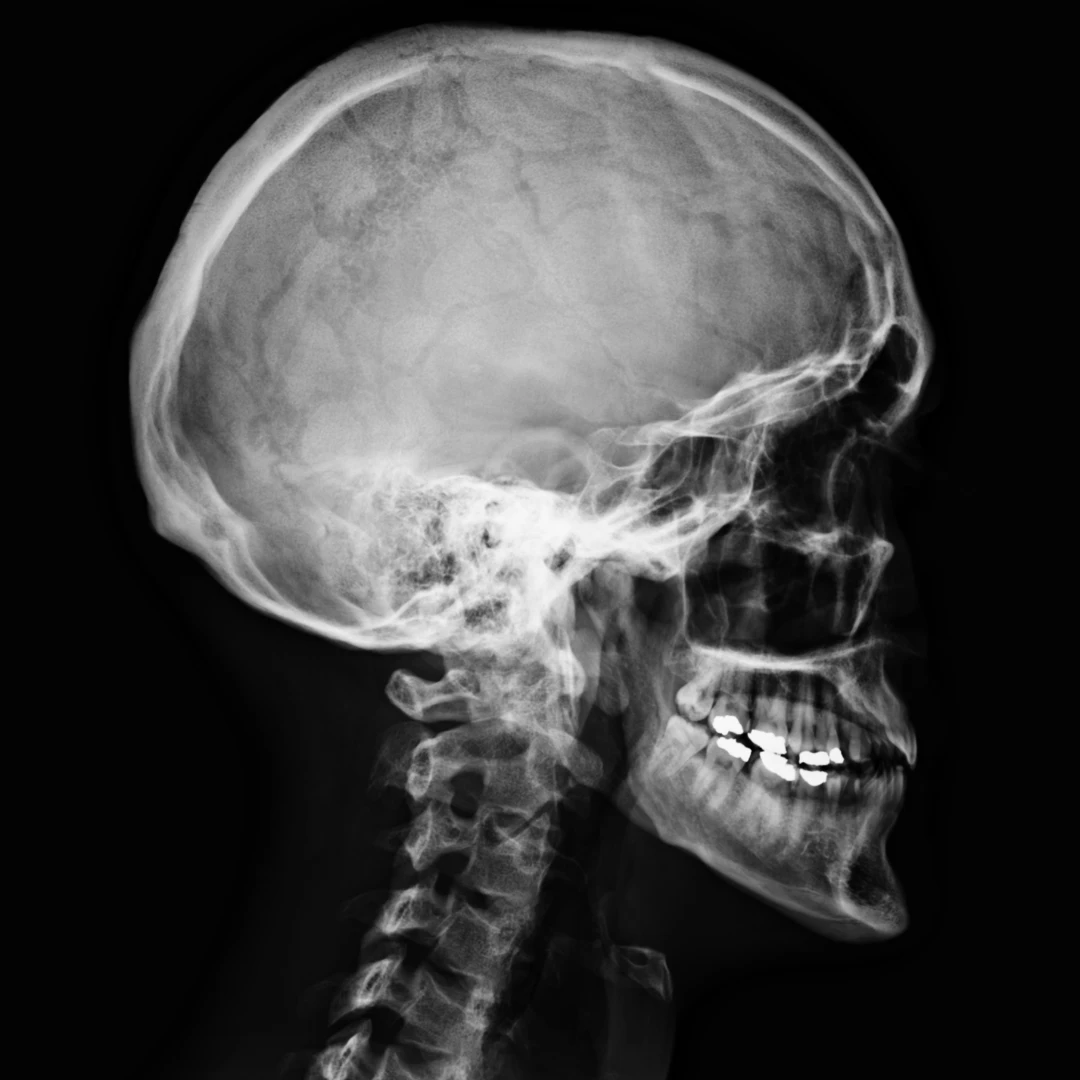

Skull/head X-ray: allows visualisation of the skull, bones on the face, and the sinus passages.